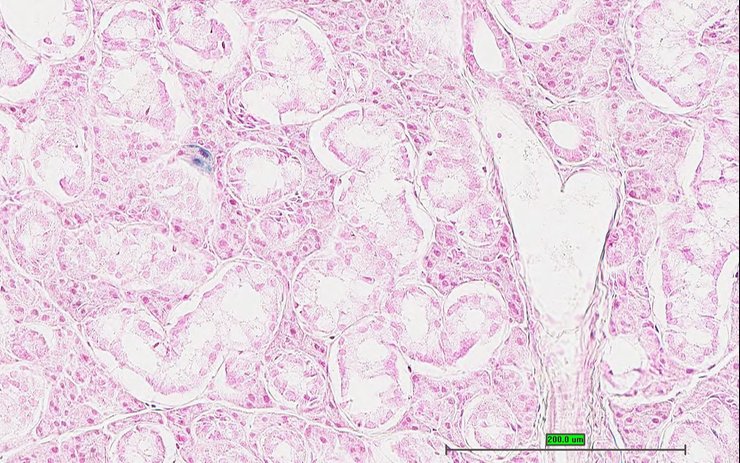

Specimen UC Davis_1866139: postnatal adult; Tmed10tm1.1(KOMP)Vlcg/Tmed10+ (more )

Structure Level Pattern Image Note

TS28: metanephros Present UC Davis_1866139 kidney

Specimen UC Davis_1866140: postnatal adult; Tmed10tm1.1(KOMP)Vlcg/Tmed10+ (more )

TS28: metanephros Present UC Davis_1866140 kidney

Specimen UC Davis_1866141: postnatal adult; Tmed10tm1.1(KOMP)Vlcg/Tmed10+ (more )

TS28: metanephros Present UC Davis_1866141 kidney